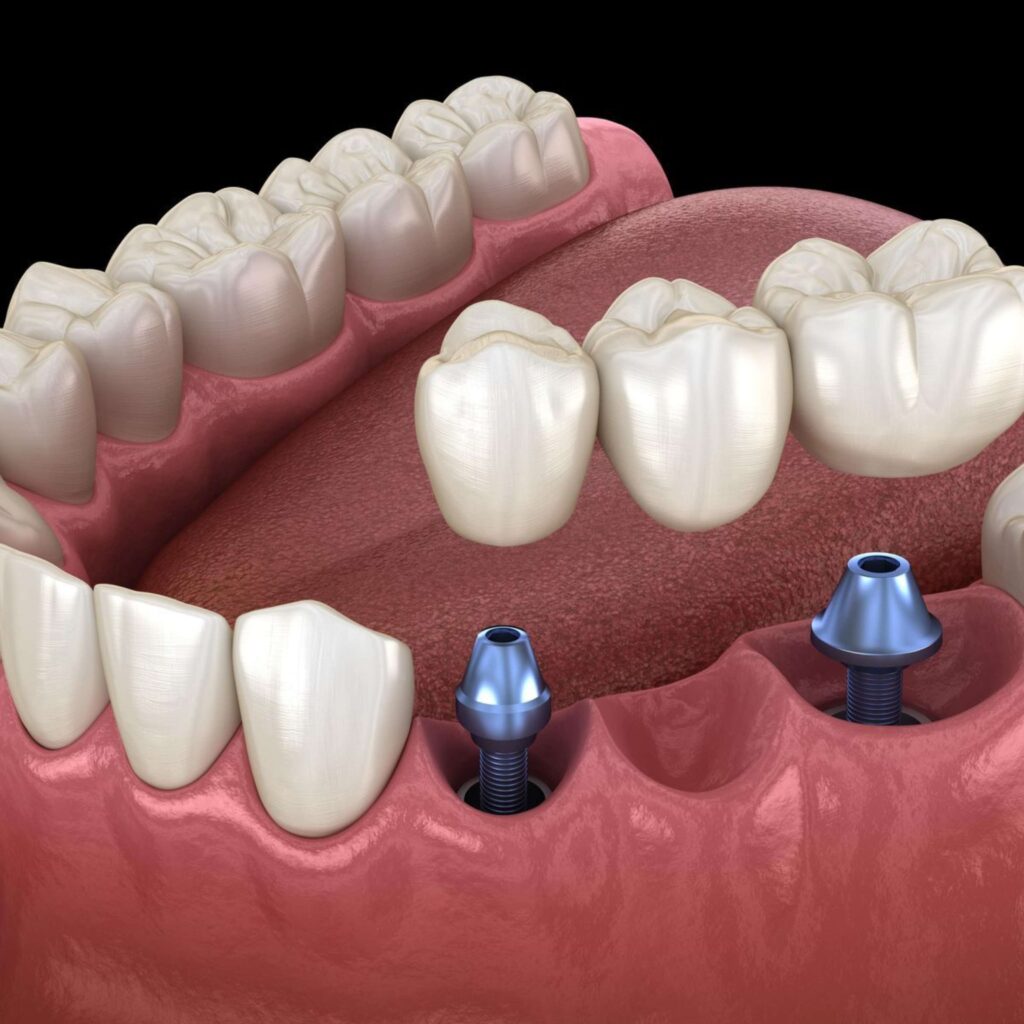

Comprehensive Curriculum: Learn the principles of prosthodontics, diagnosis, treatment planning, and techniques for removable, fixed, and implant-supported prostheses.

Fixed Prosthodontics: Crowns, Bridges, and Veneers

Implant-Supported Prosthodontics

Hi Tech Dental Academy invites aspiring dental professionals to elevate their skills with our comprehensive Prosthodontics Course. This course is specially designed to provide in-depth knowledge and hands-on training in restorative and cosmetic dentistry, including crowns, bridges, dentures, and implant-supported prosthetics. Our expert faculty ensures that you gain practical expertise alongside theoretical understanding, preparing you to handle complex cases confidently.

At Hi Tech Dental Academy, we offer an unparalleled Prosthodontics learning experience. Our expert faculty, hands-on training on real and simulated cases, and modern prosthodontic facilities ensure every student masters restorative and replacement procedures with confidence. Join us to explore fixed and removable prostheses, implant-supported restorations, occlusion management, and esthetic rehabilitation, receive professional mentorship, and thrive in a supportive environment designed to elevate your dental career.